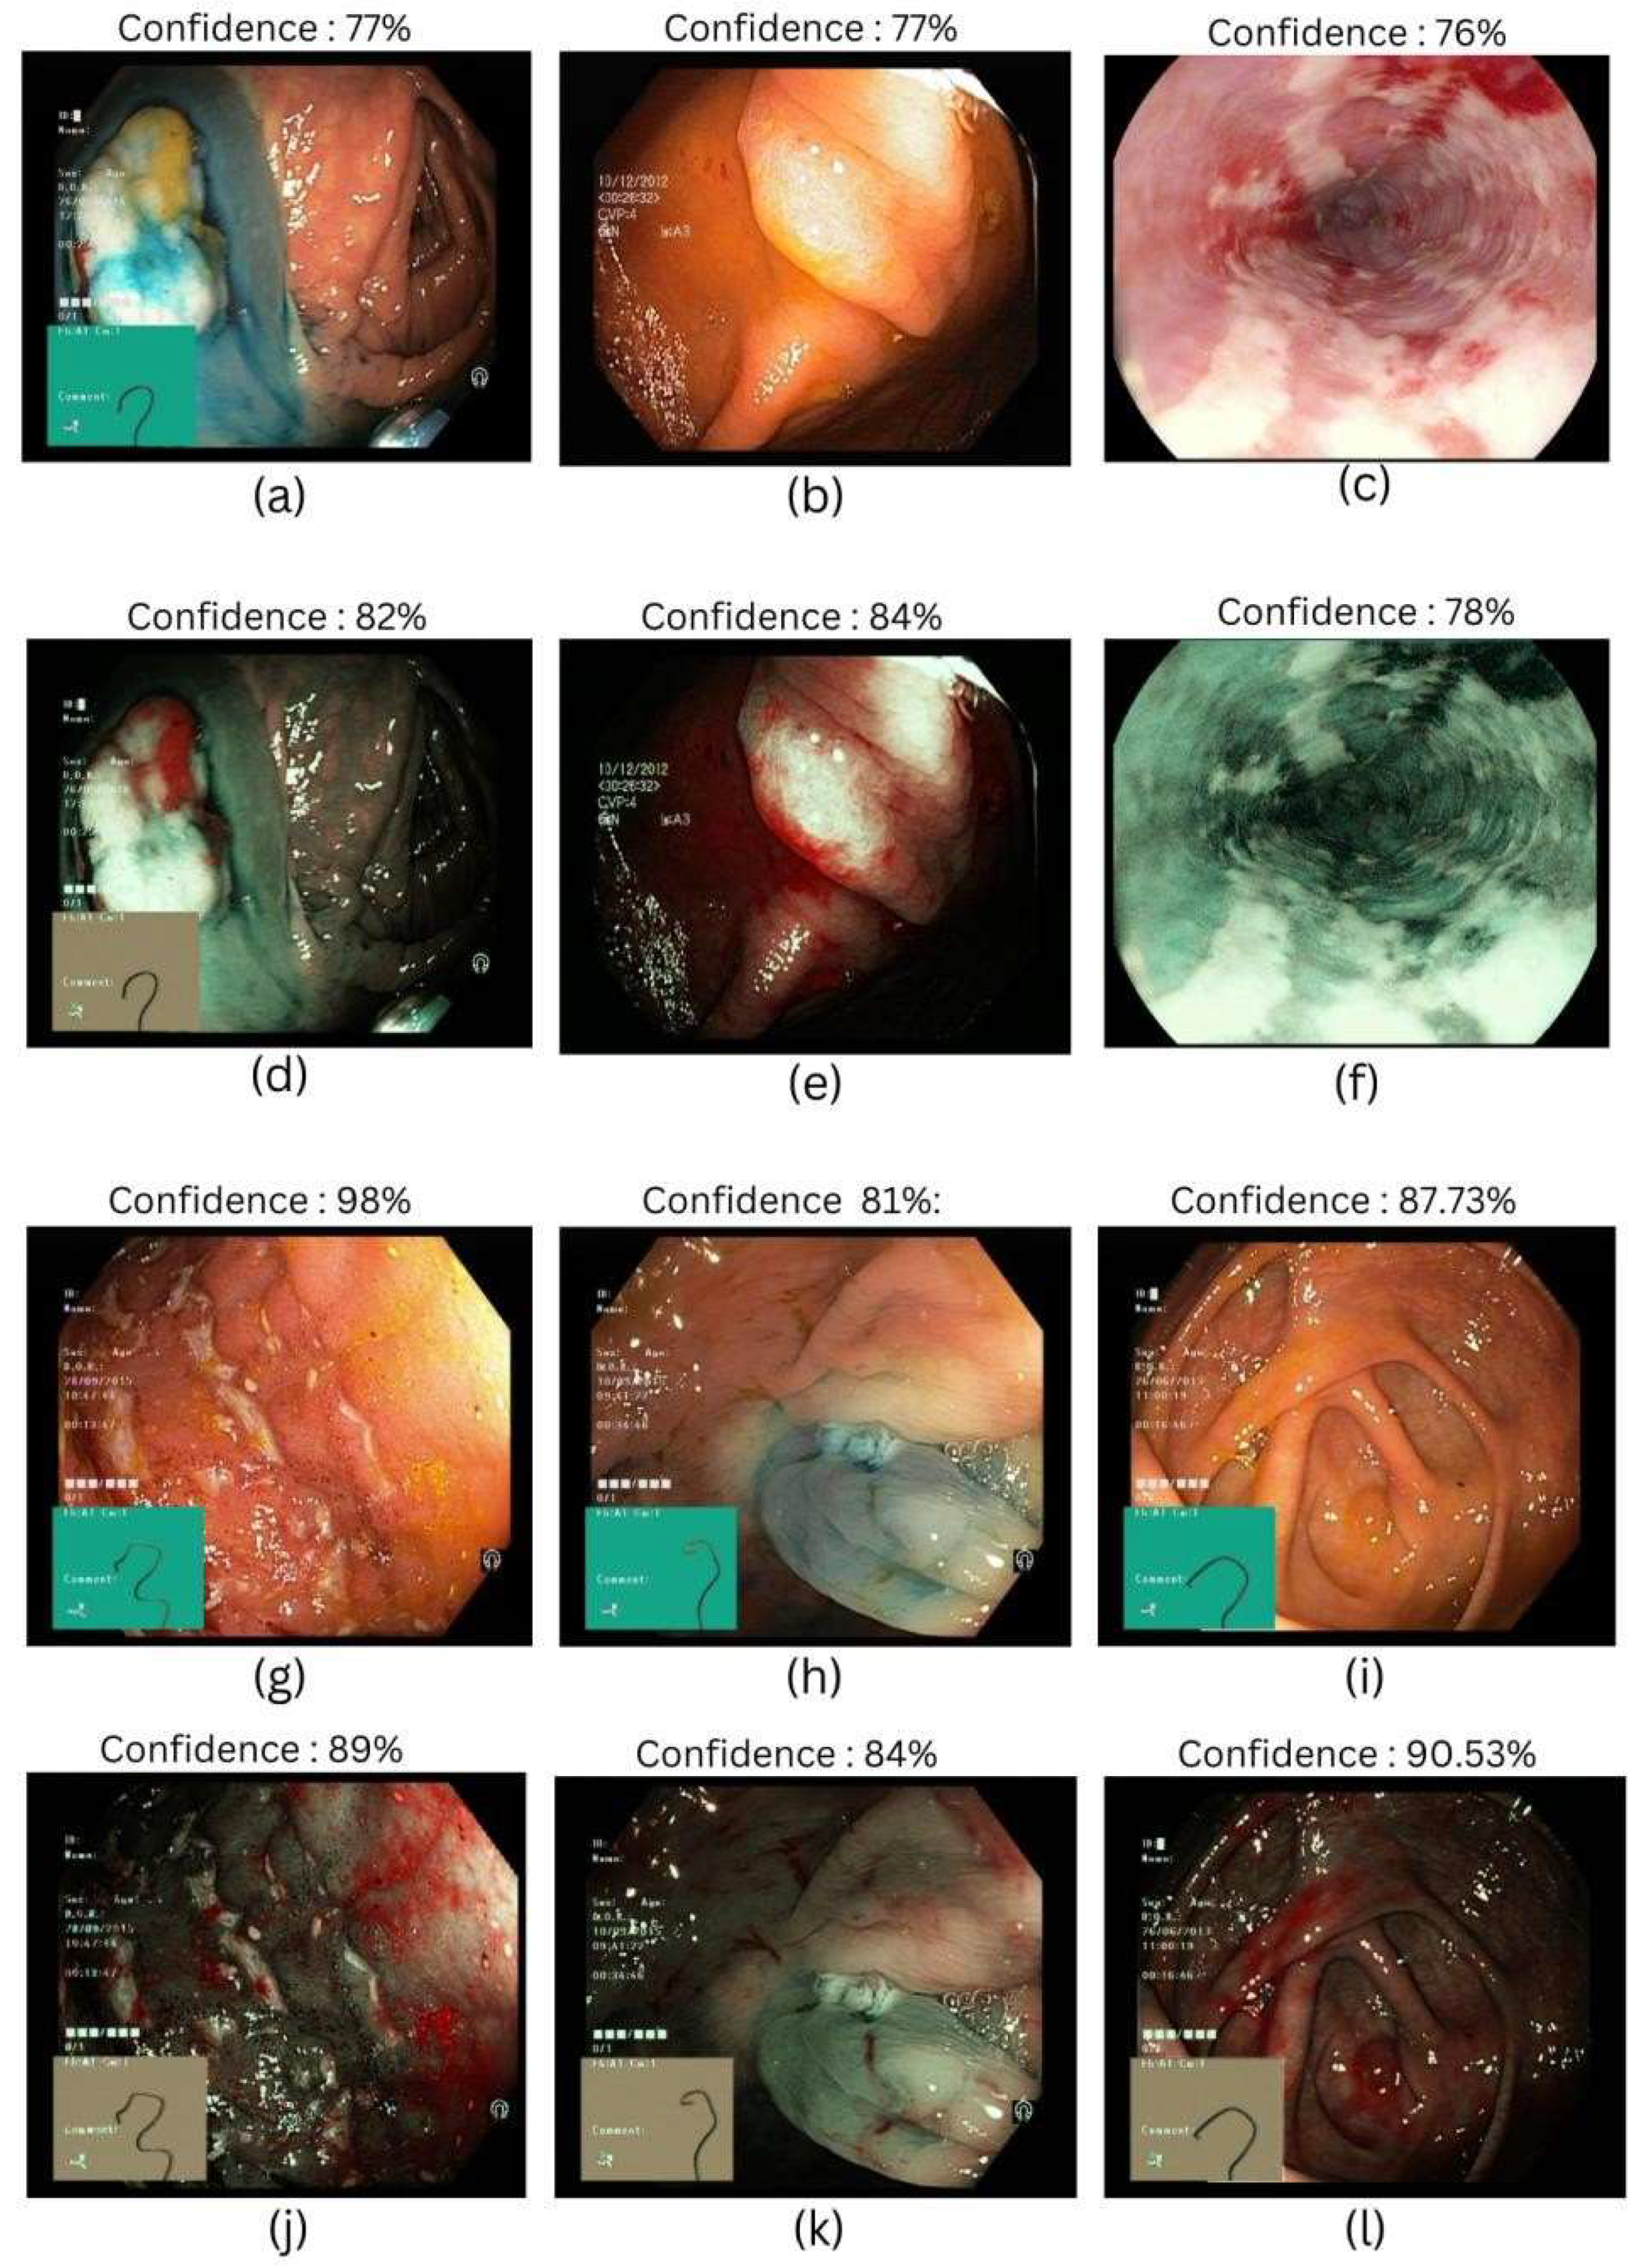

3.2. EfficientNet-B2

| SAVE | Dyed-Lifted Polyps | 86% | 80% | 83% | 86% |

| Dyed-Resection Margins | 83% | 82% | 83% | ||

| Esophagitis | 80% | 81% | 81% | ||

| Normal | 87.73% | 89.81% | 89.53% | ||

| Polyps | 84% | 86% | 85% | ||

| Ulcerative Colitis | 93% | 84% | 88% |